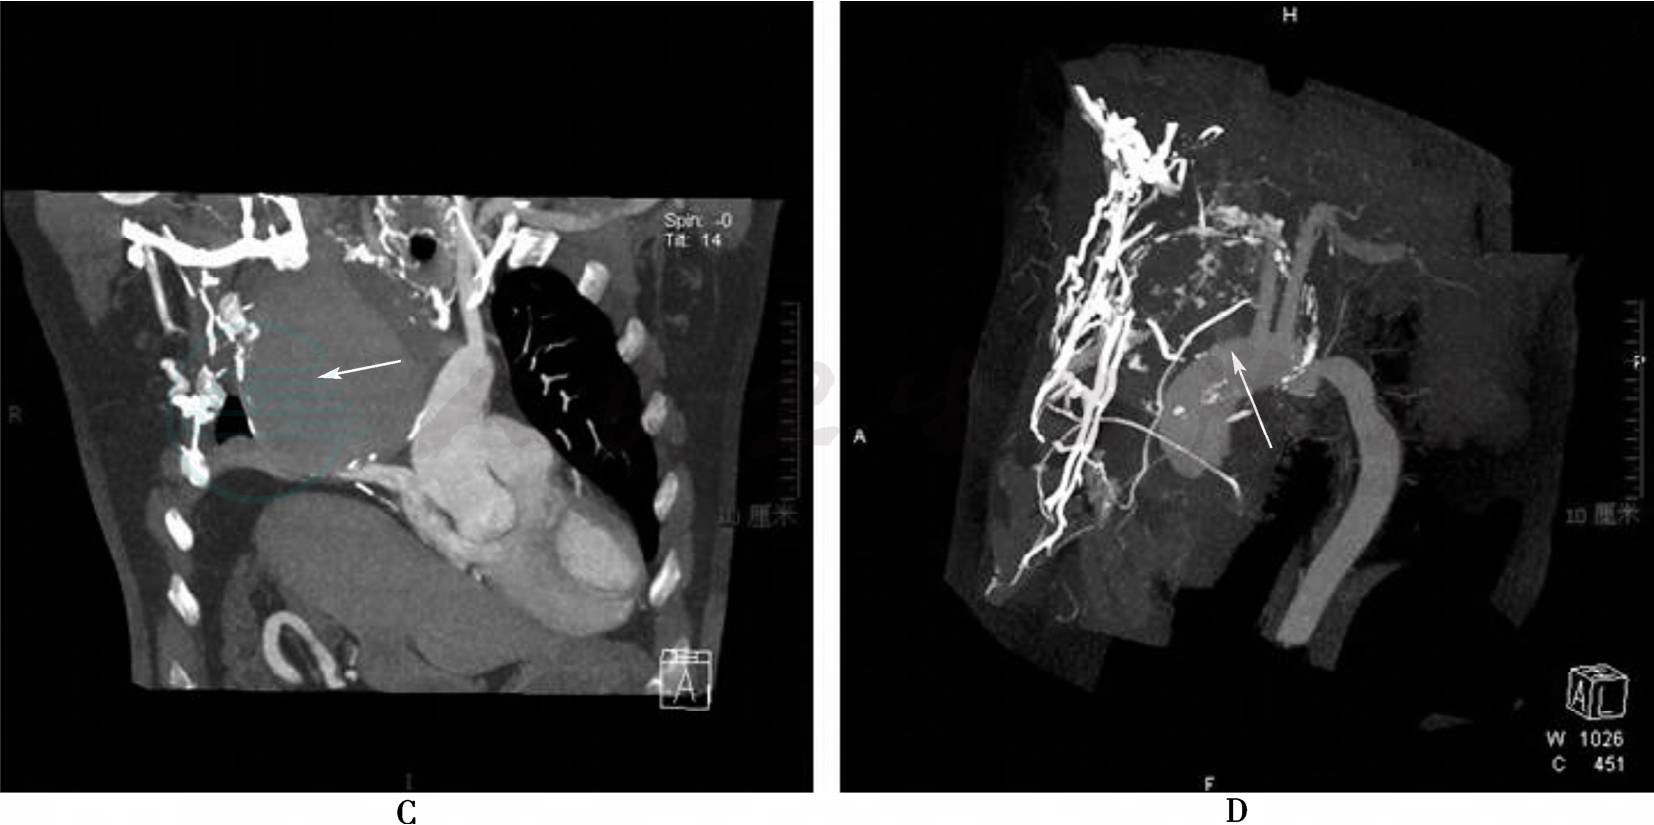

图4 胸部CT/CTA

A、C:分别CT平扫横断面、矢状面,可见无名动脉动脉瘤,与纵隔肿瘤不易鉴别 (箭头所示);B:增强CT显示无名动脉动脉瘤瘤腔强化 (箭头所示);D:CT重建无名动脉起始段显示欠清(箭头所示)